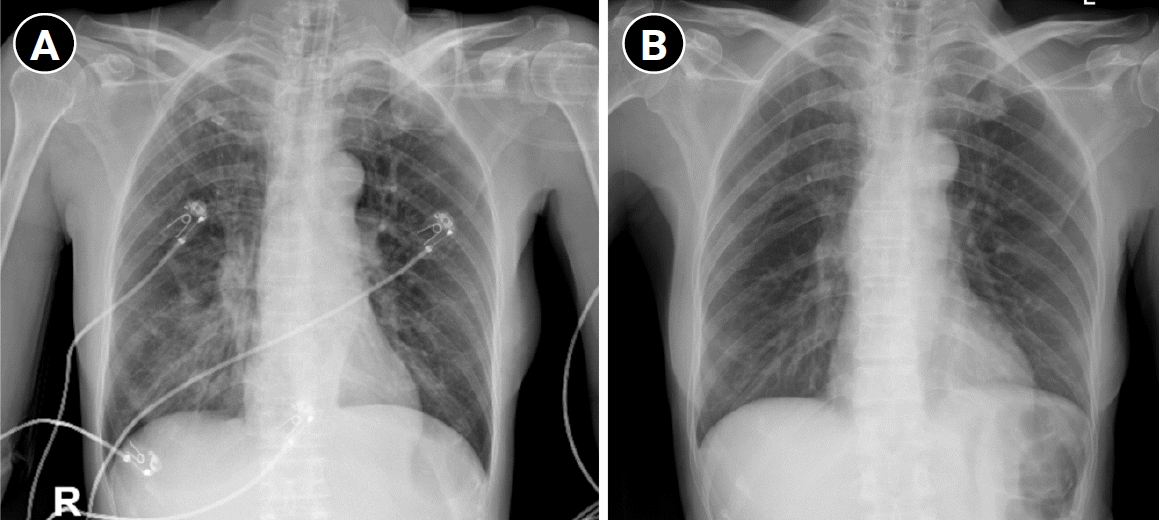

On arrival, the patient appeared critically ill and was experiencing respiratory distress. Vital signs included a temperature of 38.1 °C, respiratory rate of 33 breaths/min with intercostal retractions, pulse of 101 beats/min, blood pressure of 115/78 mm Hg, and oxygen saturation of 94% with 10 L/min oxygen administered via facemask. Neurological examination revealed fatigable proximal weakness, bulbar involvement (nasal speech and weak coughing), and a reduced gag reflex. She was able to count only to five in a single breath, consistent with impending MC. Arterial blood gas (ABG) analysis revealed a pH of 7.36, pCO2 of 46 mm Hg, pO2 of 88 mm Hg, and HCO3- of 22 mmol/L, consistent with early type II respiratory failure. Laboratory test results showed leukocytes at 9.75 ×103/µL, platelets at 131 ×103/µL, creatinine at 0.61 mg/dL, and elevated C-reactive protein at 3.2 mg/dL. Chest radiography revealed right lower lobe consolidation consistent with pneumonia, which correlated with the patient’s respiratory deterioration necessitating intubation (Fig. 1). The patient was classified as having Myasthenia Gravis Foundation of America (MGFA) Class V MG [6]. Initial oxygen support using a high-flow nasal cannula was unsuccessful, necessitating intubation and mechanical ventilation with pressure controlled bilevel positive airway pressure (fraction of inspired oxygen, 40%; positive end-expiratory pressure, 5 cm H2O; pressure support, 12 cm H2O).